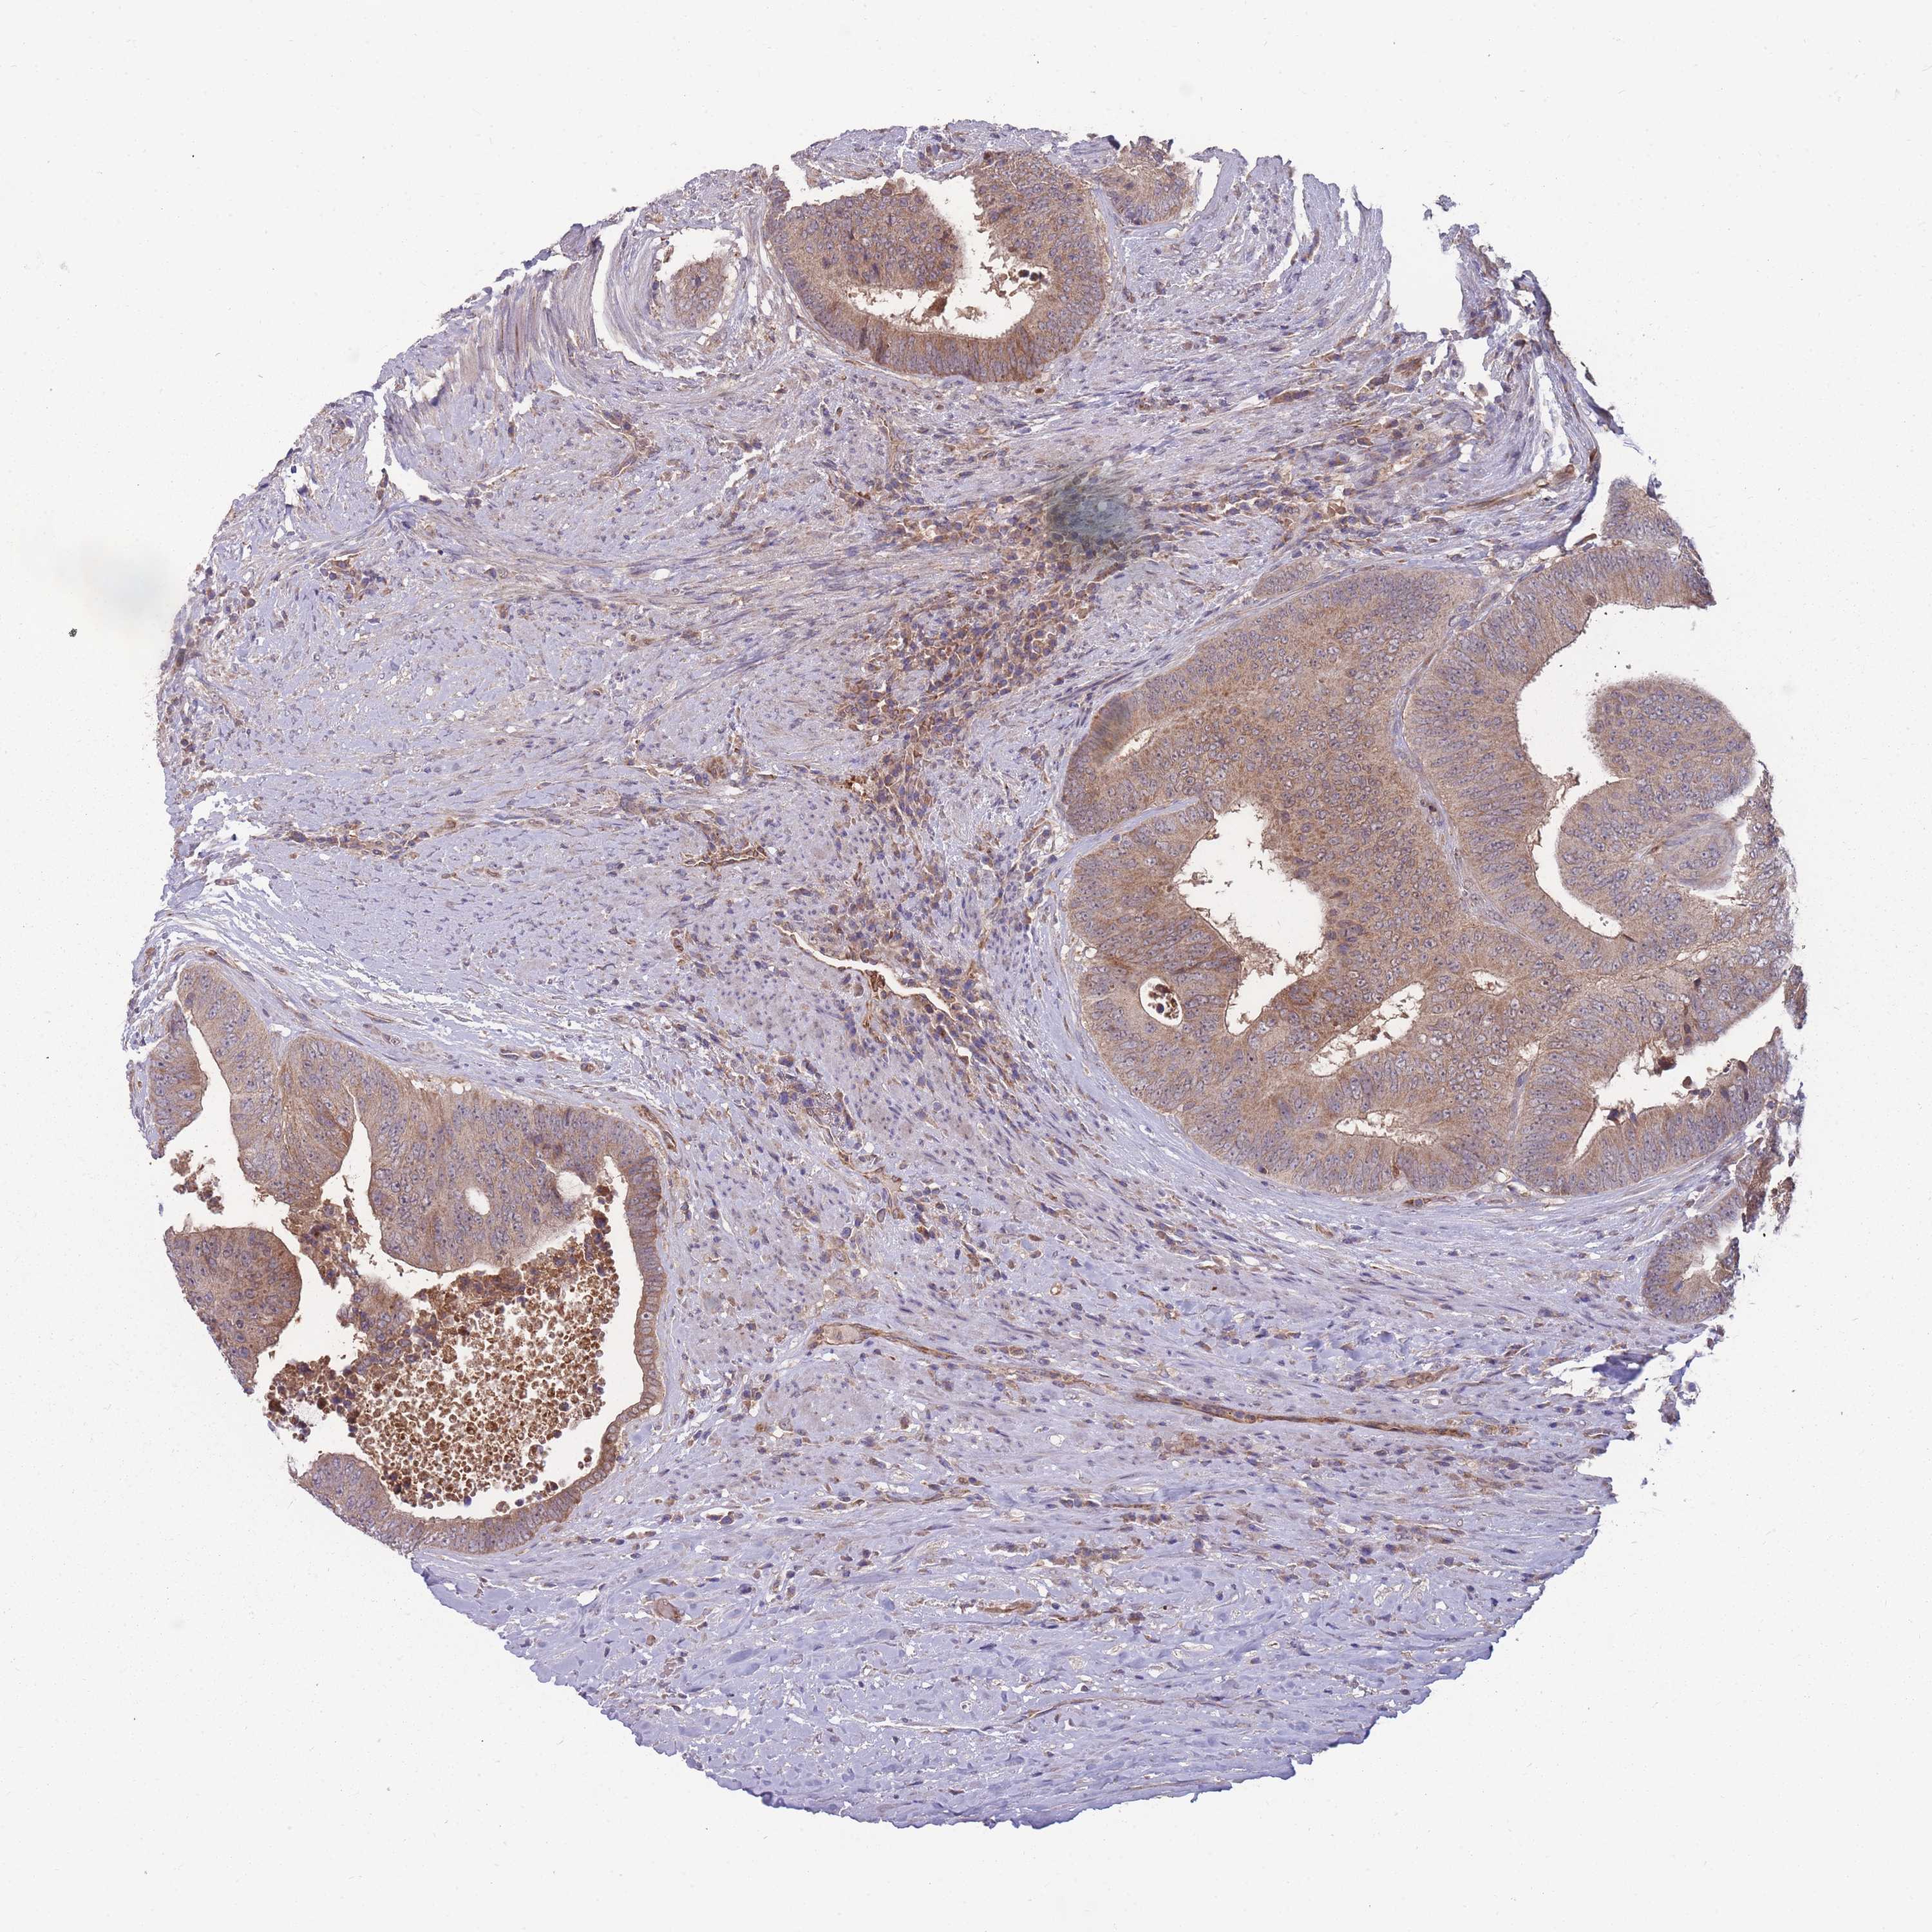

CANCER COLORECTAL CANCER Show tissue menu

ANTIBODIES

AND

VALIDATION